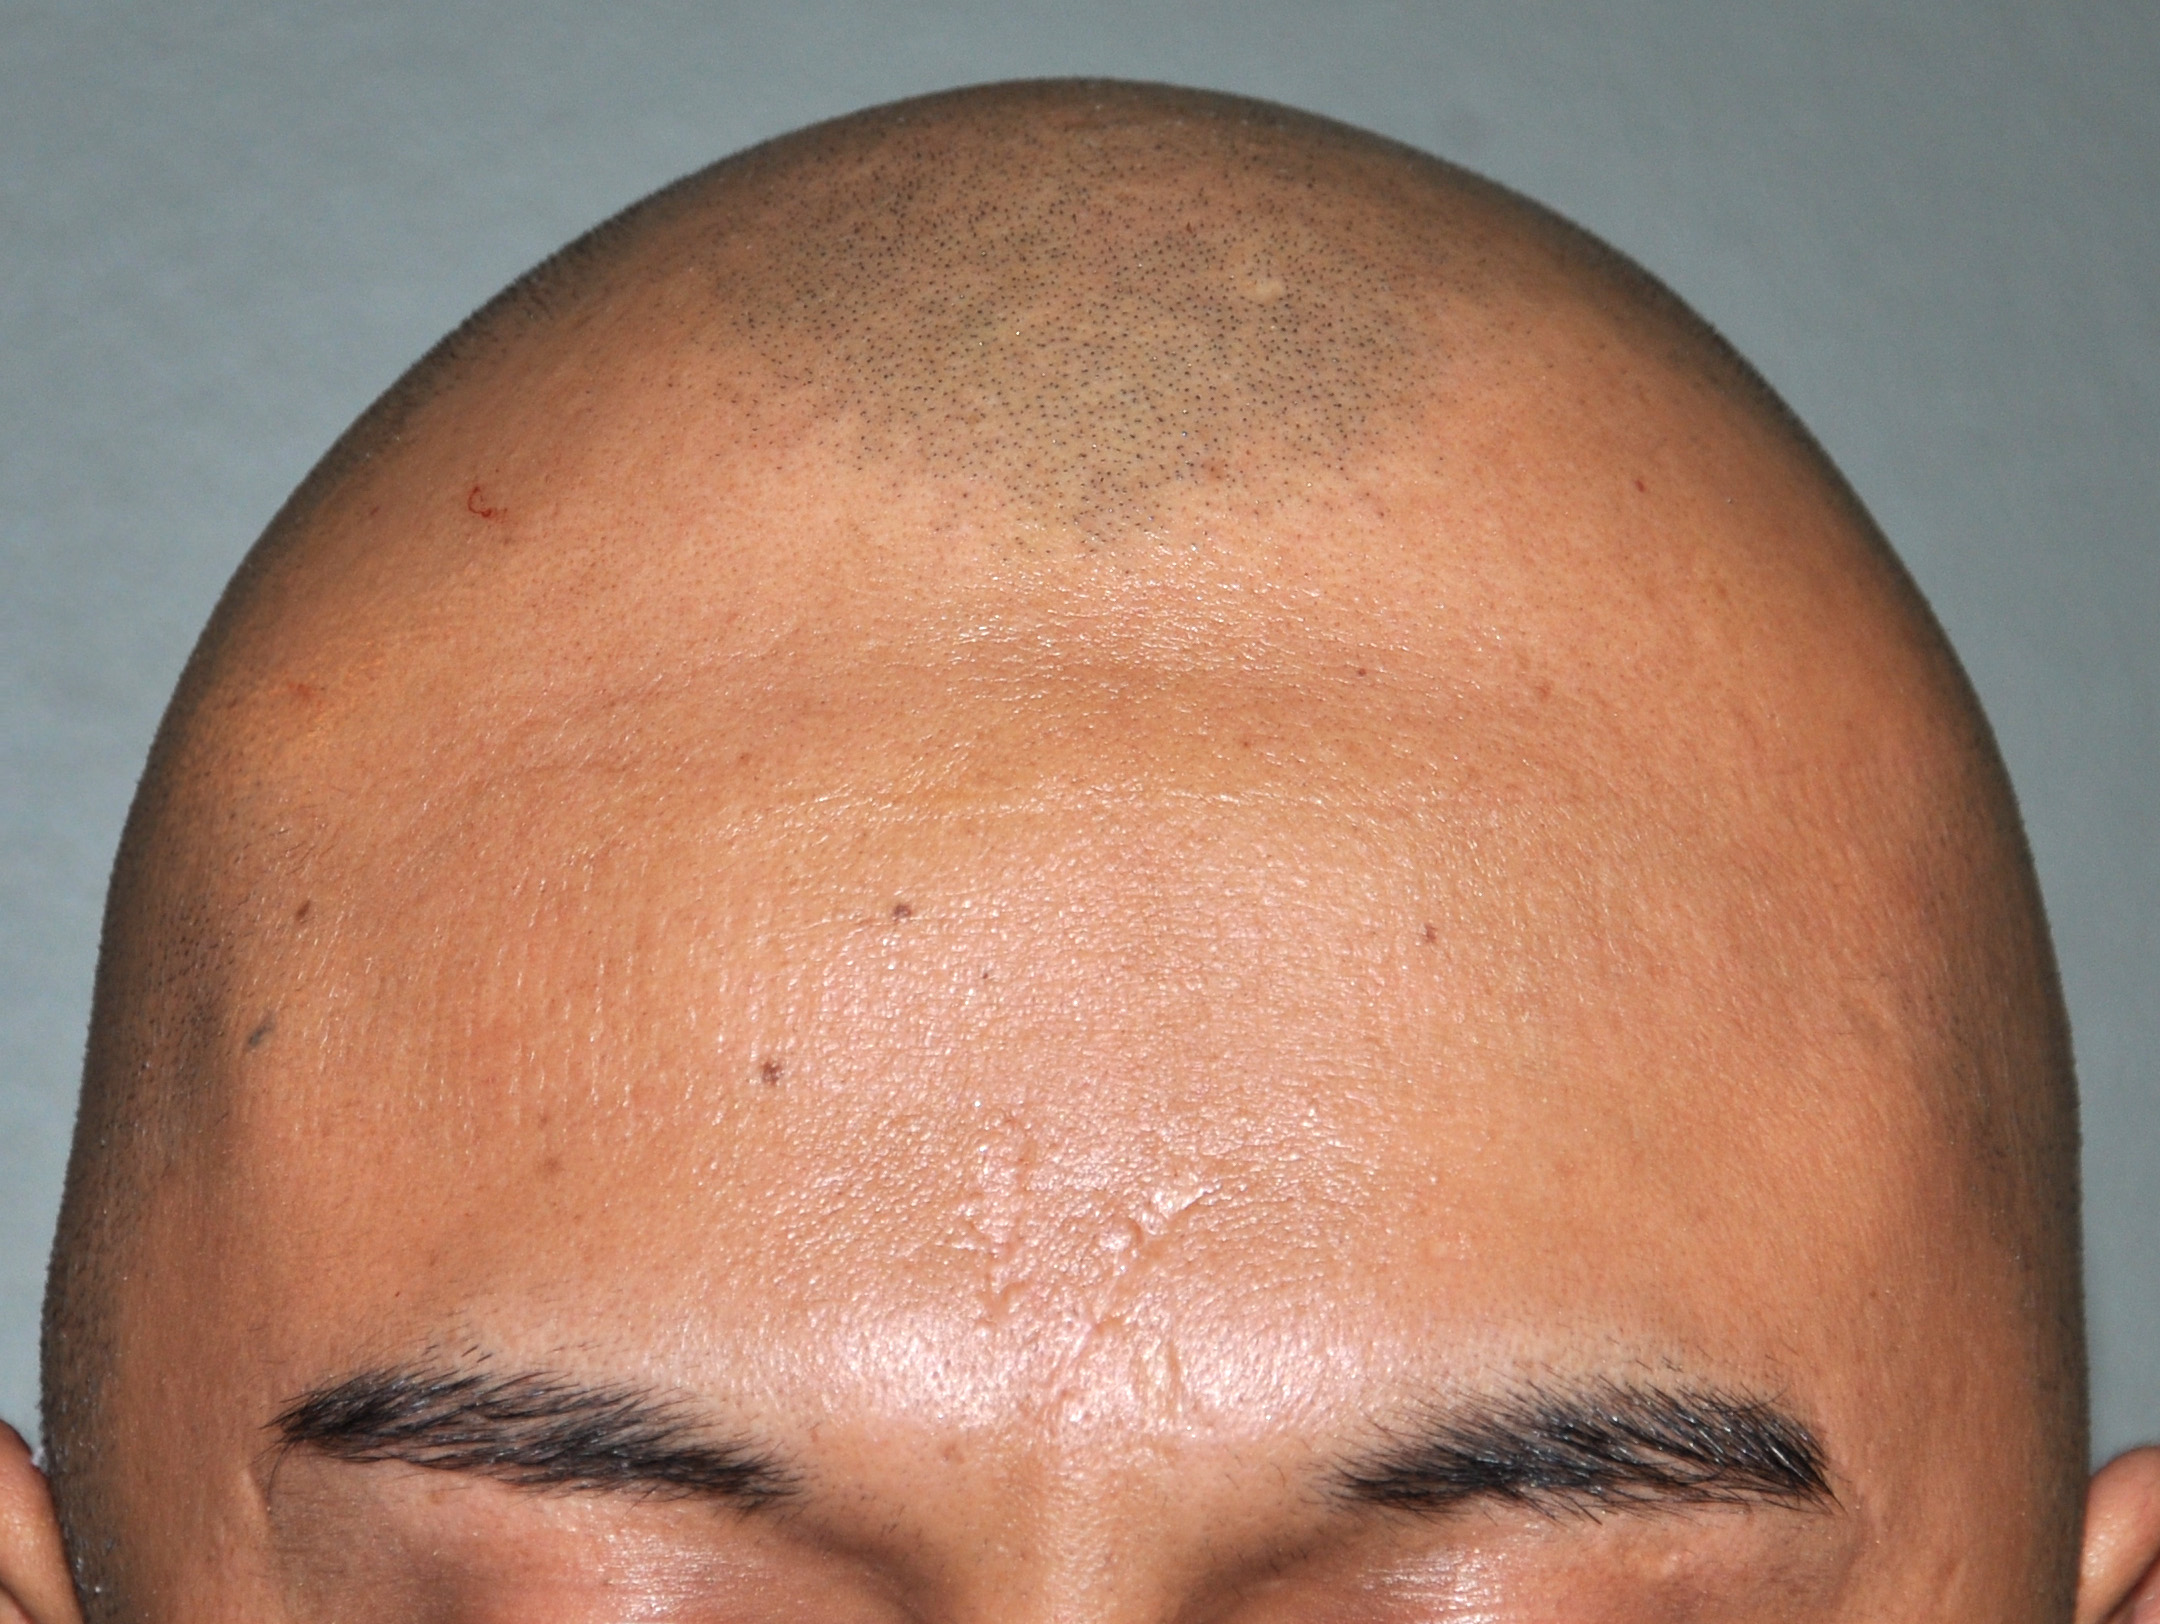

57

Scalp avulsion due to traumatic injury which left a large patch of non-hair bearing scalp.

Hair bearing scalp reconstruction using a first stage tissue expanders and second stage scalp scar removal.

Scalp avulsion due to traumatic injury which left a large patch of non-hair bearing scalp.

Hair bearing scalp reconstruction using a first stage tissue expanders and second stage scalp scar removal.